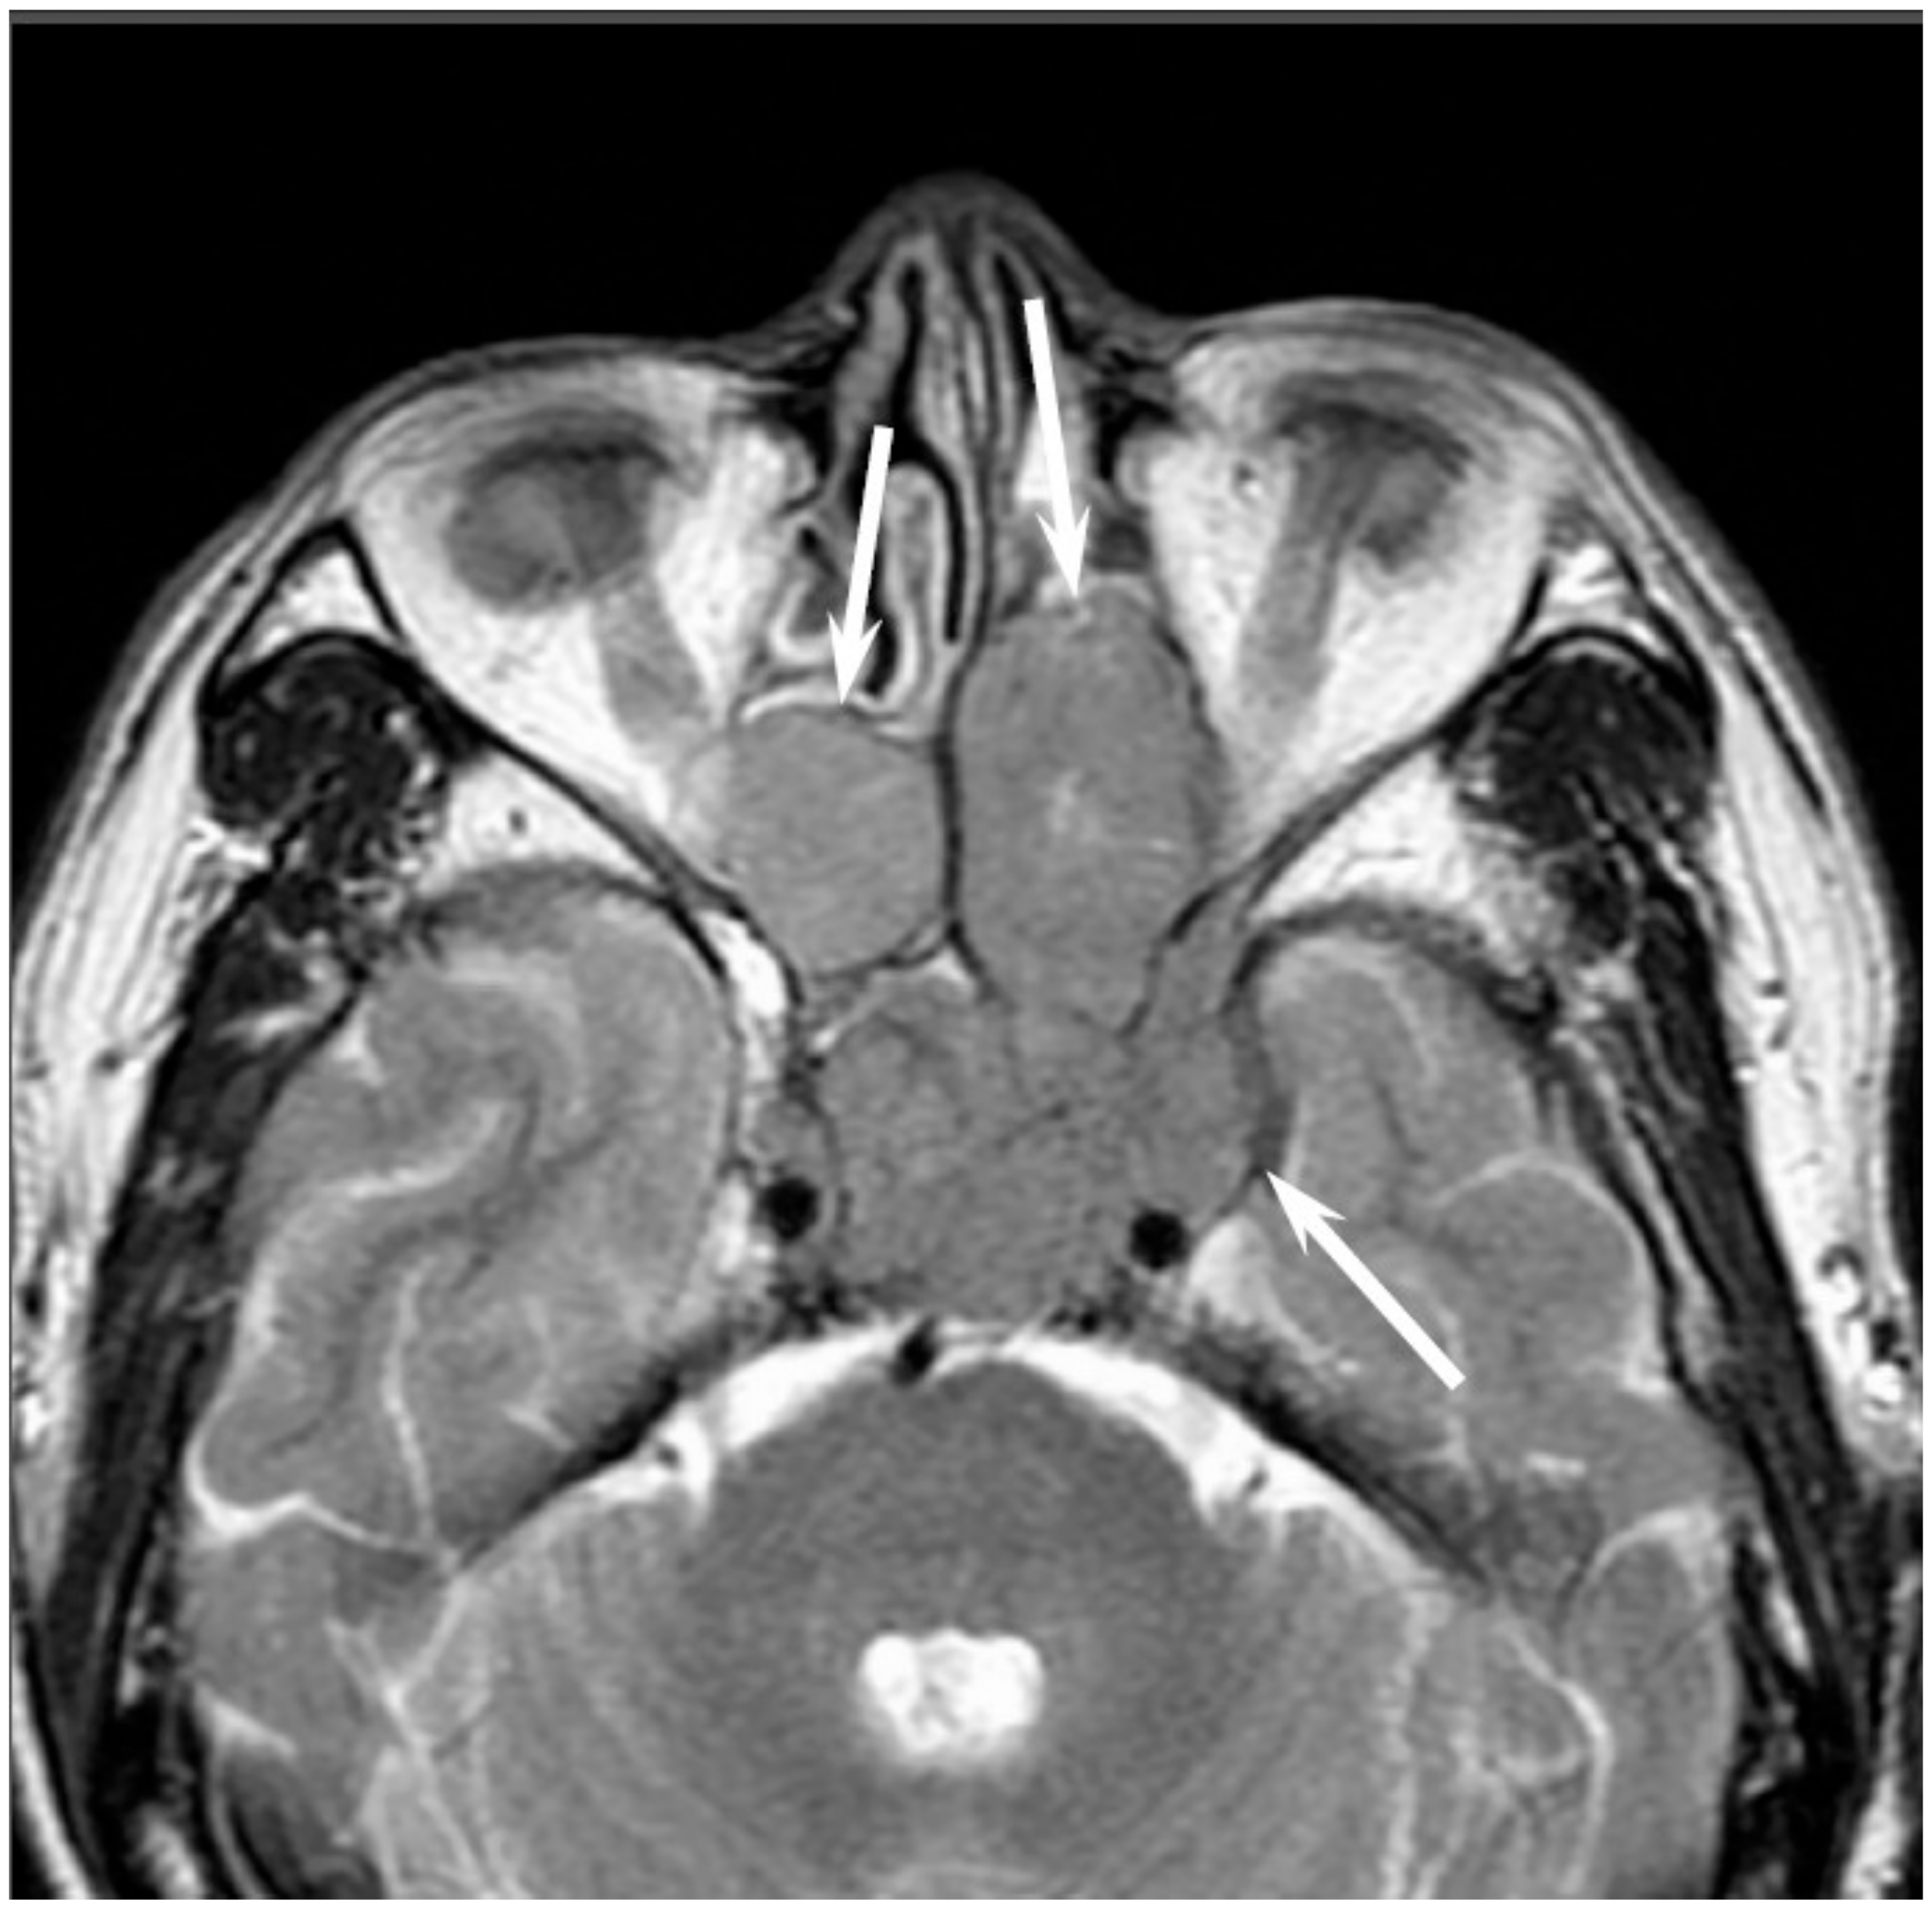

Figure 6. Extramedullary plasmacytoma of the bilateral nasal cavity. T2-weighted image showing a homogeneously isointense lesion (arrows).

On CT, EMPs typically appear as well-defined, polypoid soft-tissue masses, which exhibit homogenous enhancement. Large tumors may show areas of necrosis, destruction of the adjacent bone, infiltration of the adjacent structures, and vascular encasement [30,31]. On MRI, EMPs show isointensity on T1WI, iso- to slight hyperintensity on T2WI, and exhibit variable enhancement on contrast-enhanced T1WI [30,31] (Figure 6). Because they are highly vascularized tumors, vascular flow void may be observed within the tumor.